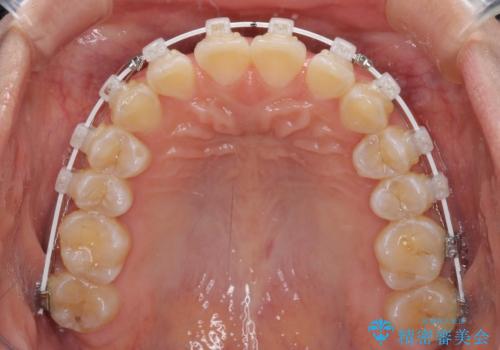

- 矯正装置

- 審美装置

正中がなかなか合わずに、2年近くの治療期間を要しました。